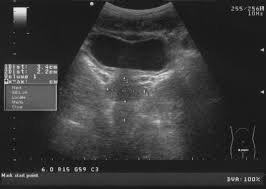

La ecografía vésico-prostática es un estudio de diagnóstico por imágenes que utiliza ultrasonido para evaluar la vejiga urinaria y la próstata. Es un procedimiento no invasivo, indoloro y seguro, ya que no utiliza radiación.

Permite analizar el tamaño, forma y estructura de la próstata, así como el estado de la vejiga y la cantidad de orina residual después de la micción.

Se realiza generalmente por vía abdominal. En algunos casos específicos puede indicarse ecografía prostática transrectal (según criterio médico).